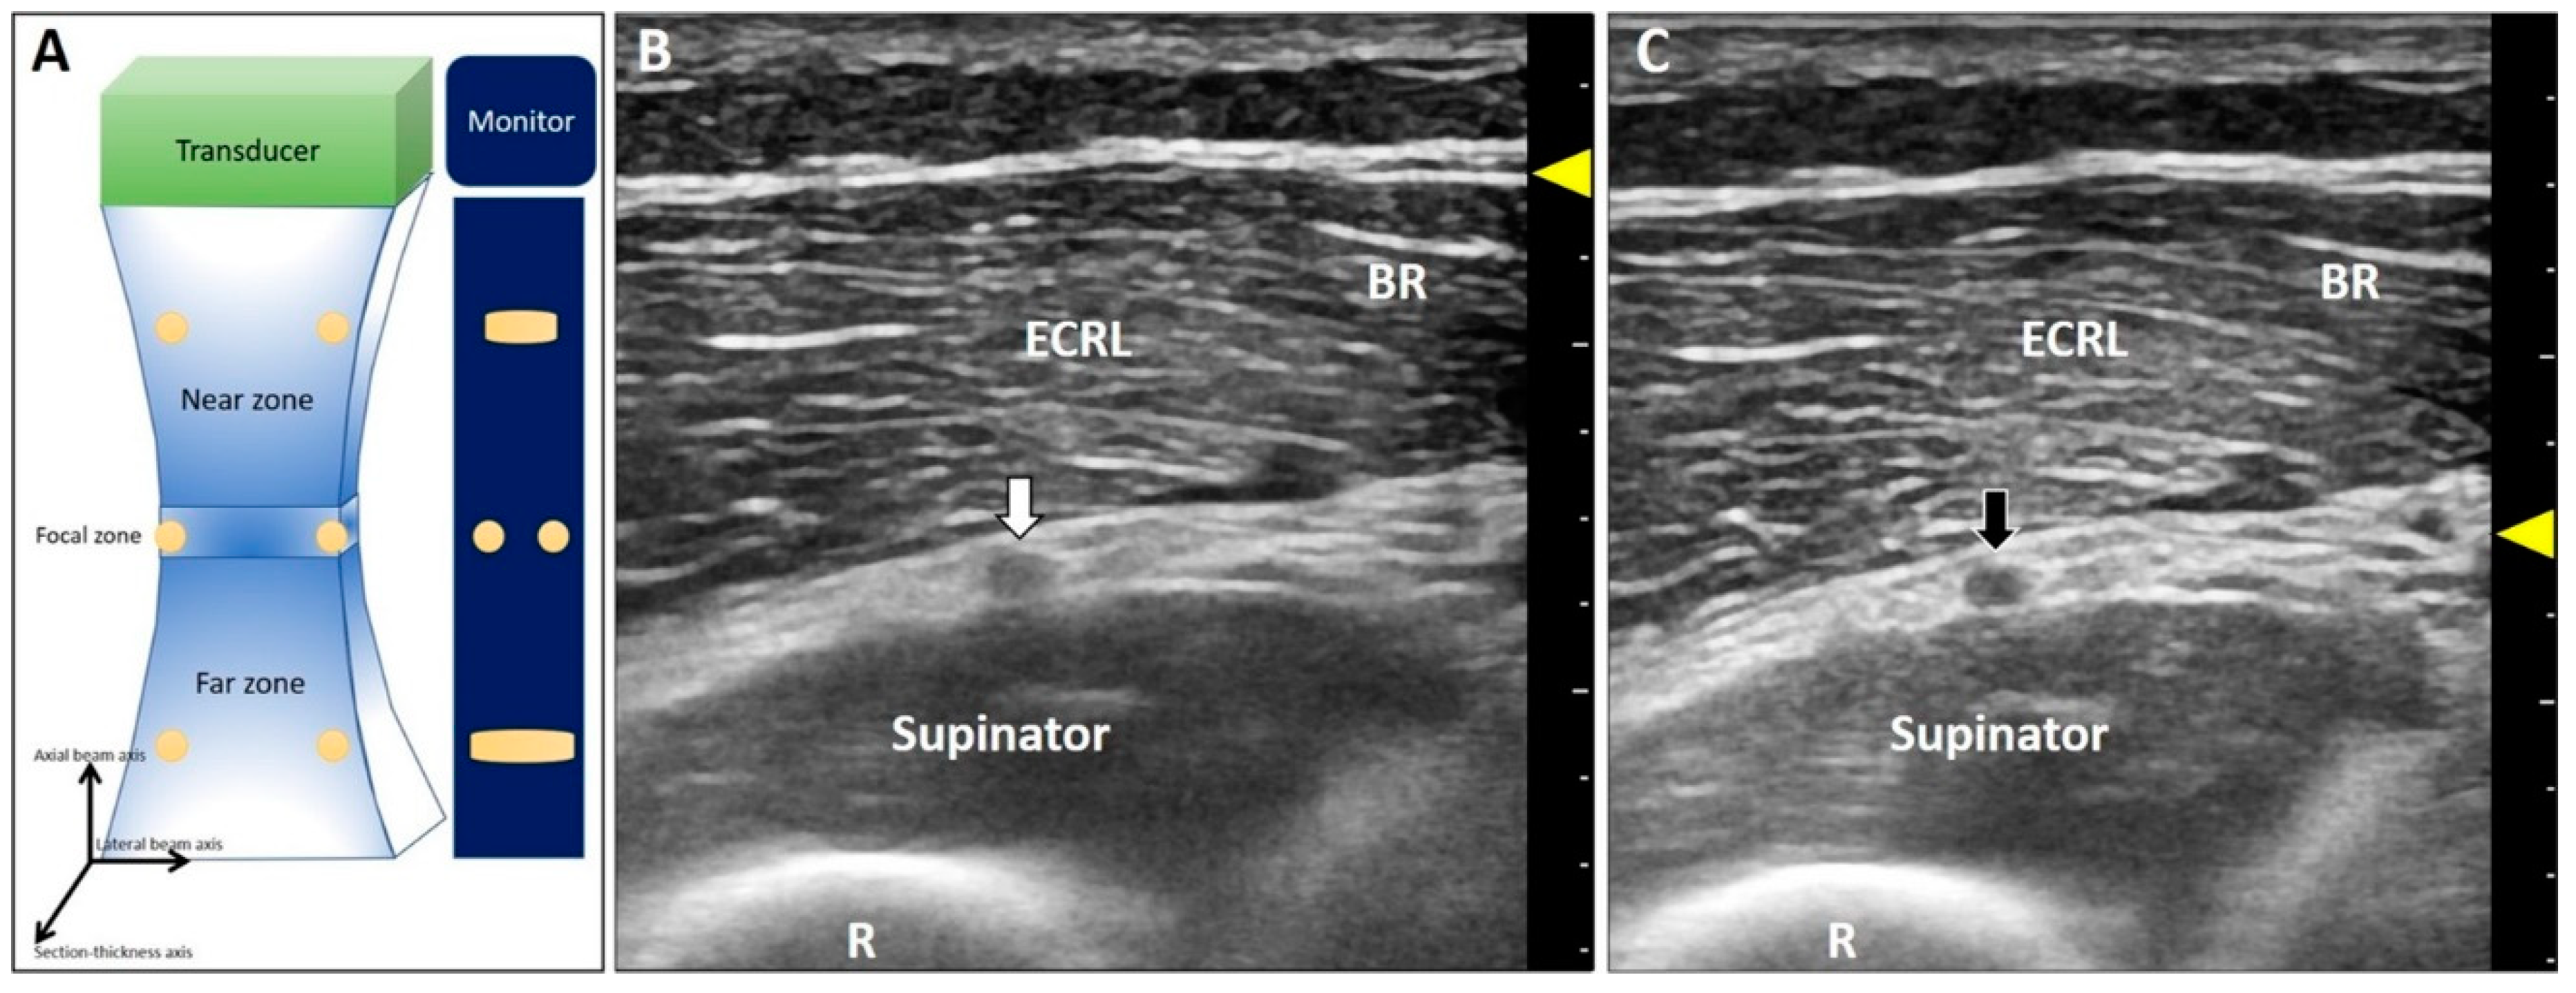

2. Improper Adjustment of the Focal Zone

2.1. Focal Zone Artifact

2.1.1. Physics

2.1.2. Clinical Examples